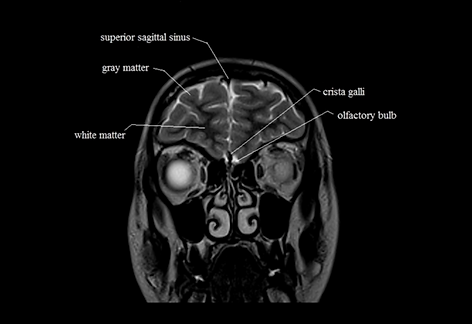

This is the coronal brain. In this slice, 6 parts of the brain are visualized. Can you identify the missing part in this slice ?